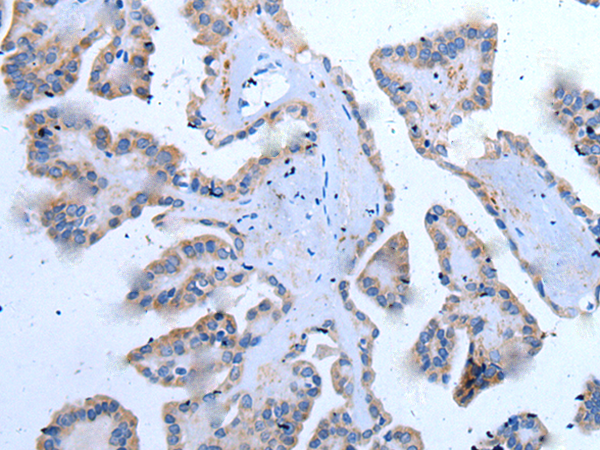

分类: 科研抗体货号: P12860别名:应用: IHC反应种属: Human, Mouse